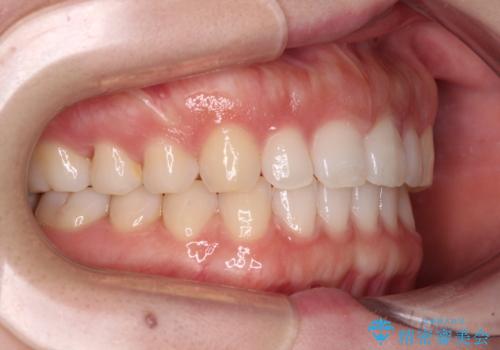

すきっ歯とオープンバイト インビザライン・ライトで改善

- 食いしばりによる顎の負担を気にして来院された患者様です。

当初は、ボツリヌス毒素による咬筋の過緊張の緩和と、睡眠時のマウスピース装着による咬合負担の解消を行いました。

オープンバイトのため、奥歯に負担のかかる咬合状態であったので、矯正治療を提案したところ、希望をされました。

すきっ歯程度の軽度の歯列不正であったため、インビザライン・ライトにより咬合改善を行うこととしました。

オープンバイトやすきっ歯は、舌突出癖によりあっという間に後戻りをするため、矯正治療前からトレーニングを行っていただき、更には後戻り防止のワイヤーリテーナーを併用しています。